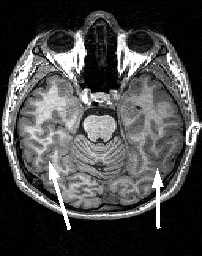

МРТ головного мозга. Аксиальный срез. Коллатеральная борозда (стрелки).

МРТ головного мозга. Аксиальный срез на уровне Варолиева моста. Височно-затылочная борозда (стрелки).